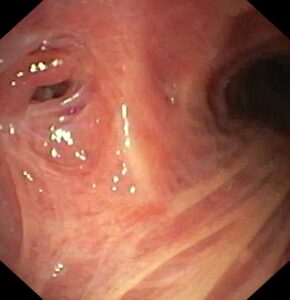

В эндоскопическом атласе обычно представлены изображения и видео, полученные во время процедур, проводимых врачами-эндоскопистами. Эти изображения и видео могут использоваться для обучения студентов медицинских учебных заведений, повышения квалификации медицинских работников, а также для консультации врачей при диагностике и лечении различных заболеваний.